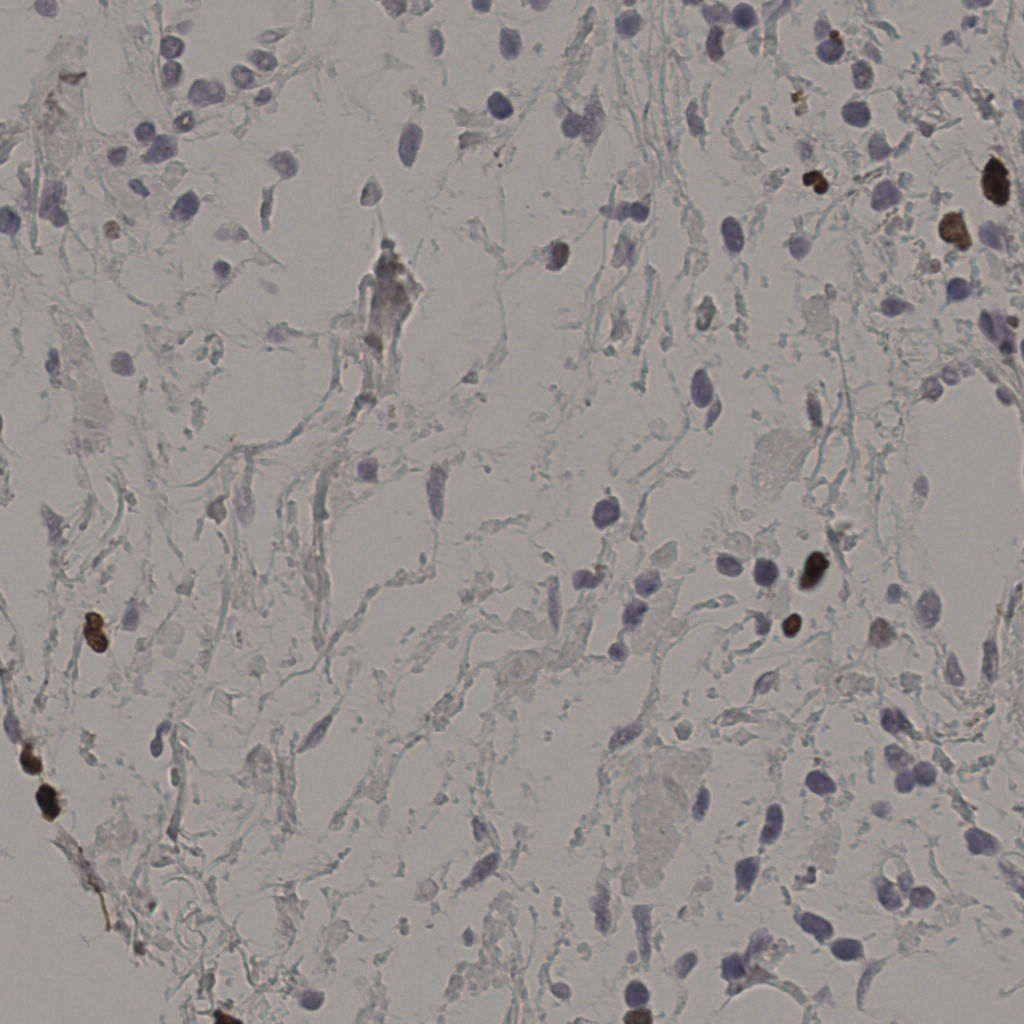

17.75%

Ki67 指数

阴 7986 阳 1723

切片统计

总切片 2640

有效 412

已标记 412

有效率 16%